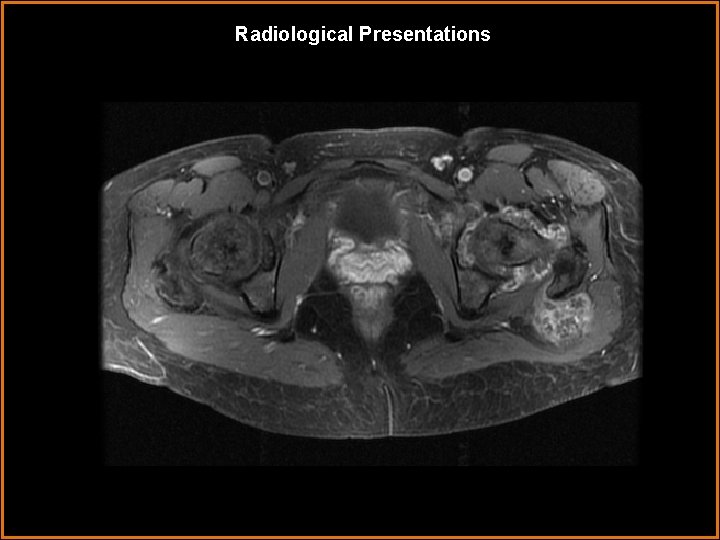

Findings and Differentials Findings: AP radiograph of the left hip demonstrates pressure erosions of the femoral neck, the central portion of the acetabulum and the fovea centralis of the femoral head. Extensive calcification around the hip joint is also seen. CT demonstrates erosions of the femoral head and acetabulum and numerous calcified bodies of similar size in the hip joint and extensive synovial dissecting pouches surrounding the joint. Some calcification has “ring-and-arc” configuration. MRI showes diffuse synovial process of low signal intensity on T 1, high signal intensity on. T 2 and contrast enhancement. Lower signal intensity regions on T 2 and T 1 post contrast images are present. Extension to the surrounding bursa and soft tissue is also seen. Differentials: • The imaging findings are virtually pathognomonic for synovial osteochondromatosis.

Discussion Synovial osteochondromatosis represents an uncommon benign neoplastic process with hyaline cartilage nodules in the subsynovial tissue of a joint, tendon sheath, or bursa. The nodules may enlarge and detach from the synovium. The knee, followed by the hip, in male adults are the most commonly involved sites and patient population. Radiologic findings are frequently pathognomonic. Radiographs reveal multiple intraarticular calcifications (70%– 95% of cases) of similar size and shape, distributed throughout the joint, with typical "ring-and-arc" chondroid mineralization. Extrinsic erosion of bone is seen in 20%– 50% of cases. Computed tomography (CT) optimally depicts the calcified intraarticular fragments and extrinsic bone erosion. Magnetic resonance (MR) imaging findings are more variable, depending on the degree of mineralization, although the most common pattern (77% of cases) reveals low to intermediate signal intensity with T 1 weighting and very high signal intensity with T 2 -weighting with hypointense calcifications. These signal intensity characteristics on MR images and low attenuation of the nonmineralized regions on CT scans reflect the high water content of the cartilaginous lesions. CT and MR imaging depict the extent of the synovial disease (particularly surrounding soft-tissue involvement) and lobular growth. Treatment is surgical synovectomy with removal of chondral fragments; recurrence rates range from 3% to 23%. Malignant transformation to chondrosarcoma is unusual (5% of cases) and, although difficult to distinguish from benign disease, is suggested by multiple recurrences and marrow invasion. Recognizing the appearances of synovial osteochondromatosis, which reflect their underlying pathologic characteristics, improves radiologic assessment and is important to optimize patient management.